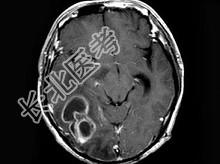

- 单项选择题男,47岁, 发热、头痛、呕吐1周,MRI检查, 最可能的诊断是 ( )

A、脑转移瘤

B、脑脓肿

C、胶质瘤

D、血吸虫性脑病

E、未见异常